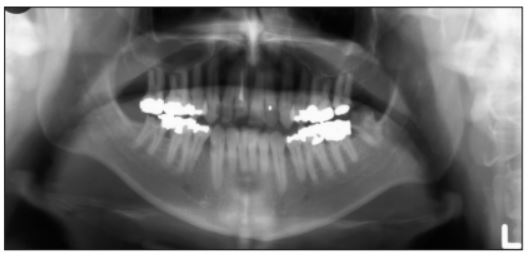

Al giorno d'oggi, le radiografie panoramiche offrono al dentista una eccellente soluzione per conoscere tutti i dettagli della bocca del paziente, ma è possibile riscontrare una serie di problemi comuni. In questo articolo andremo ad esporre le più frequenti problematiche e le relative soluzioni per risolverle, considerando i passaggi basici per ottenere una buona radiografia panoramica.

Inoltre, è consigliato revisare con una certa frequenza le macchine a raggi-X. Esistono molte opzioni sul mercato, come per esempio i raggi-X panoramici che, grazie a questa tecnologia di radiografia panoramica, permettono al dentista un esame dentale con raggi-X bidimensionali (2D) che catturano immagini della bocca intera in una sola presa, includendo i denti, le mandibole inferiori e superiori e le strutture e i tessuti circostanti.

Il principale vantaggio dei raggi X panoramici rispetto ai raggi X intra-orali tradizionali, è che la piastra per una radiografia panoramica è incorporata dentro alla macchina e non è necessario collocarla dentro alla bocca. Nel nostro catalogo, potrai trovare una grande varietà di raggi-X panoramici con distinte prestazioni.